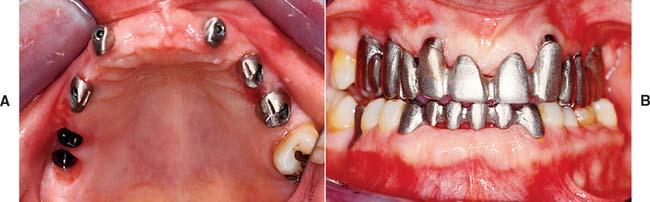

For completely edentulous patients who require nonremovable restorations, there are two implant options: a complete metal-resin fixed dental prosthesis and a metal-ceramic fixed dental prosthesis (Figs. 13-48 to 13-50).

Fig. 13-48 A to D, A metal-ceramic implant restoration may be indicated if adequate bone and soft tissue contours are available.

Fig. 13-49 Radiograph showing fixed restorations supported by seven implants in the maxilla and six in the mandible. Radiograph of patient in Fig. 13-48.

Fig. 13-50 Metal-resin restorations are the treatment of choice for edentulous patients with moderate bone resorption.

The complete metal-resin fixed dental prosthesis is a cast alloy framework with processed denture resin and teeth. It is typically supported by a minimum of five implants in the mandible and six in the maxilla. One major determining factor for selecting this option is the amount of bone and soft tissue that has been lost. For patients who have had moderate bone loss, the prosthesis restores both bone and soft tissue contours.

The metal-ceramic prosthesis also requires a minimum of five implants in the mandible and six in the maxilla. It can be made esthetically pleasing only if bone loss is minimal and is best suited for patients who have recently (within 5 years) lost their natural teeth. For patients with severe bone loss, there is probably only one option: a removable restoration (Fig. 13-51).